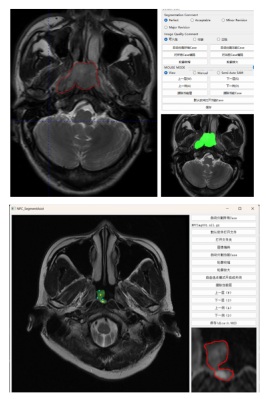

针对鼻咽癌等华南地区高发的肿瘤影像自动化分析的需要,学院智能医学影像分析团队致力于攻克研究医学影像中目标自动或半自动化的完整勾画方案。利用深度学习的方法攻克了影像中模糊边界的目标分割方法,相比传统方法的分割性能提升了25%。基于大模型技术研制了鼻咽癌半自动完整勾画软件系统。目前,该软件应用于中山大学肿瘤防治中心的头颈部MRI影像的鼻咽癌筛查工作中,大大地减轻了医生对目标勾画的工作量。

图5. 鼻咽癌影像筛查系统